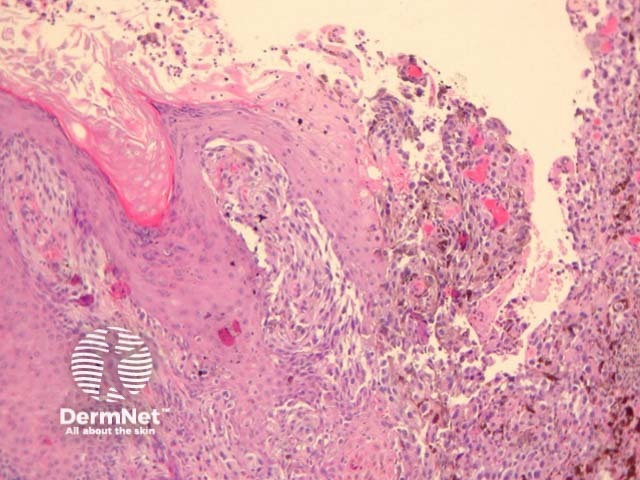

Cutaneous metastasis of melanoma can cause diagnostic confusion. The metastatic melanoma may invade the dermis or subcutis and form a nodular tumour mass without invasion of the overlying epidermis (figure 1). The pattern of growth may mimic a benign intradermal naevus at low power (figure 1) but at high power examination the nuclear atypia is usually obvious, there may be mitoses and there is minimal evidence of maturation (decrease in cell size) with descent in the dermis (figure 2). Usually the lack of epidermal involvement is a good clue the tumour is a metastasis from another site but sometimes the metastasis may invade the epidermis and closely simulate a primary melanoma.

Rarely, melanoma which has metastasised to the dermis may closely mimic a blue naevus (blue naevus-like melanoma, figures 3,4). This can cause considerable diagnostic difficulty and be impossible to correctly recognise without clinical information.

Figure 1

Figure 2

Figure 3

Figure 4